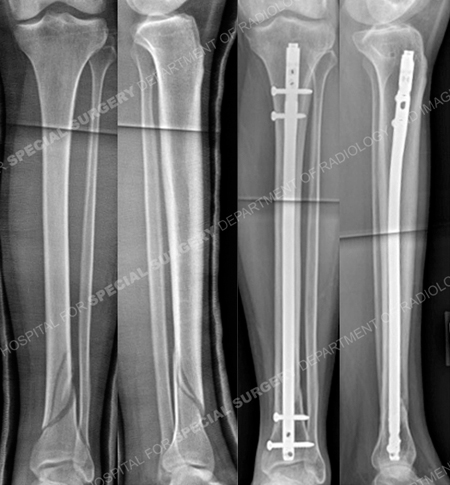

A 22 year-old male baseball player fell while running and sustained a twisting injury to his left lower extremity. He was taken to a local hospital and radiographs revealed a spiral oblique distal 1/3 tibia fracture. He was initially placed in a long leg cast and referred to David L. Helfet, MD at the Orthopedic Trauma Service of Hospital for Special Surgery for definitive management. Open reduction and internal fixation (ORIF) was performed with insertion of an intramedullary nail and locking screws. He returned for regular follow-up and healed uneventfully. At the time of his latest follow-up visit, 9 months following fracture surgery, he has excellent radiographic and clinical results including a healed distal tibia fracture in good alignment, resolution of pain, and a return to pre-injury activities including baseball.

Anteroposterior (AP) and lateral injury radiographs (left images) reveal a spiral oblique distal third tibia fracture and AP and lateral radiographs 9 months following surgery (right images) reveal a healed distal tibia fracture.